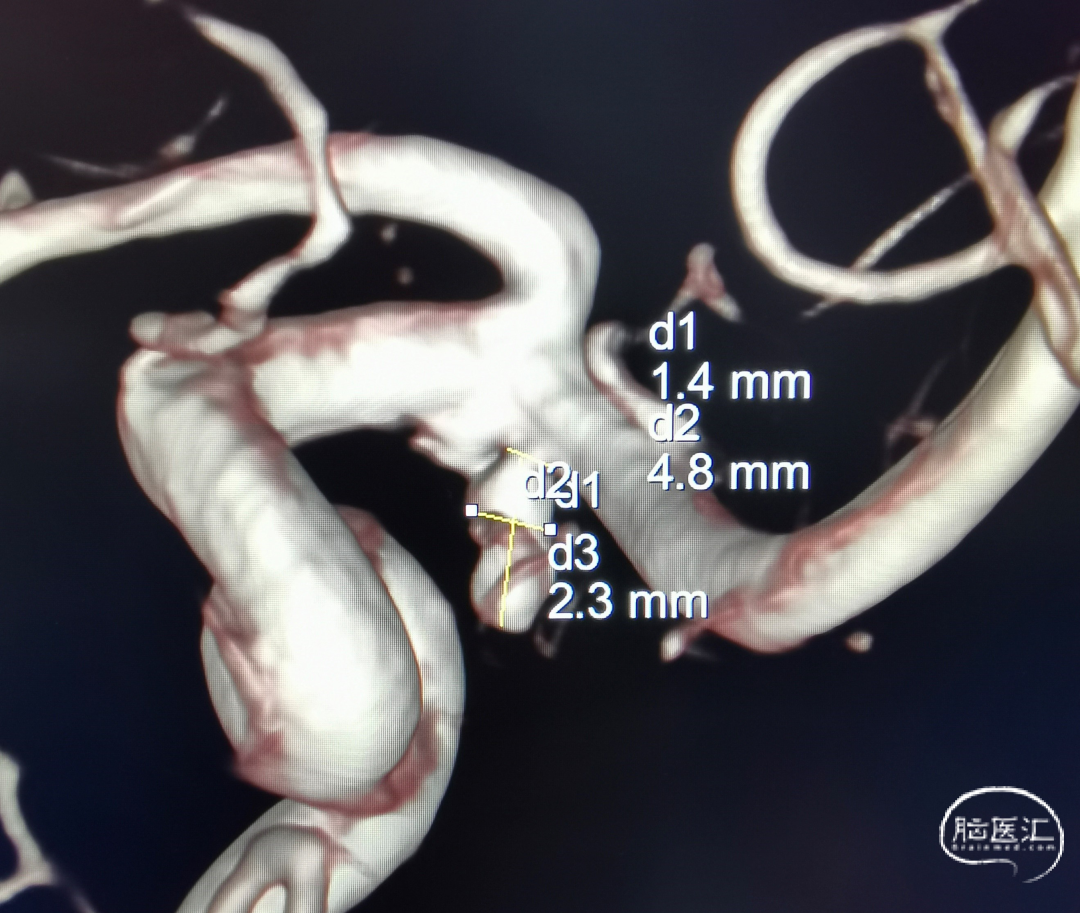

左侧大脑中动脉M1段起始处动脉瘤,大小2.3mm*4.8mm,瘤颈宽1.4mm。主动脉III型弓,左侧颈内动脉血管非常迂曲,患者血管条件较差。

2.治疗策略:

窄颈动脉瘤,且瘤体呈长条形,尽量使用单微导管完成栓塞。动脉瘤与载瘤动脉成反向夹角,需通过微导管塑形将头端送入瘤体内,并稳定输送弹簧圈。对于下端路径的迂曲,如主动脉弓、降主动脉以及髂股动脉等,采用6F长鞘,代替常规的8F导引导管构成通道,具有一定优势[1]。综合考虑,使用长鞘配合近段硬远端较软的中间导管,简单便捷;给微导管提供稳定的支撑,并且不会造成血管痉挛等并发症,提高本次手术的安全性。因此,选择沃比Esperance®远端通路导管。